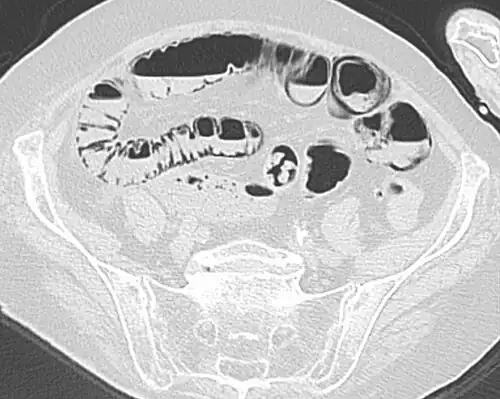

Pneumatosis intestinalis (also called intestinal pneumatosis, pneumatosis cystoides intestinalis, pneumatosis coli, or intramural bowel gas) is pneumatosis of an intestine, that is, gas cysts in the bowel wall.[1][2] As a radiological sign it is highly suggestive for necrotizing enterocolitis. This is in contrast to gas in the intestinal lumen (which is relieved by flatulence). In newborns, pneumatosis intestinalis is considered diagnostic for necrotizing enterocolitis, and the gas is produced by bacteria in the bowel wall.[3] The pathogenesis of pneumatosis intestinalis is poorly understood and is likely multifactorial. PI itself is not a disease, but rather a clinical sign. In some cases, PI is an incidental finding, whereas in others, it portends a life-threatening intra-abdominal condition.